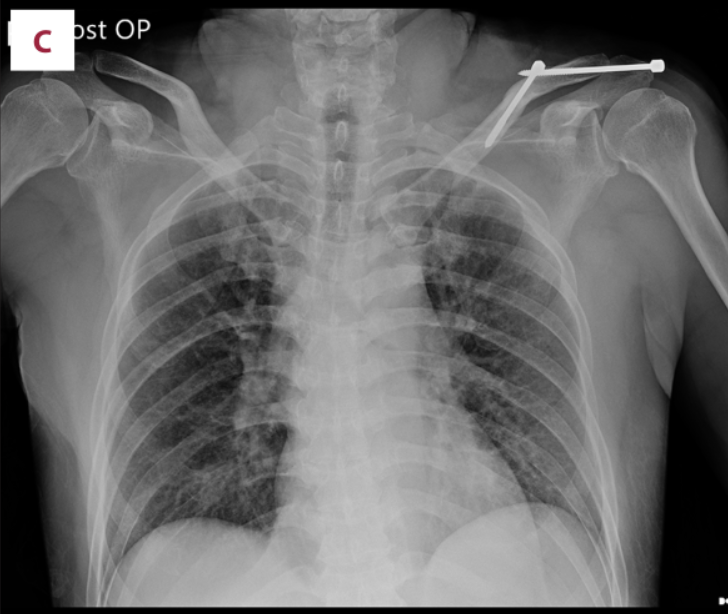

(A)在c臂图像增强器的帮助下,用克氏针将锁骨推入解剖位置进行闭合复位。(B)从肩峰尖端穿过肩锁关节(ACJ)至锁骨远端,用Knowles钉在锁骨远端后侧实现皮质锚定。采用Knowles销固定时,采用拉力螺钉技术保持ACJ空间。(C)术后x线片显示经皮Knowles针闭合复位治疗ACJ脱位复位良好。